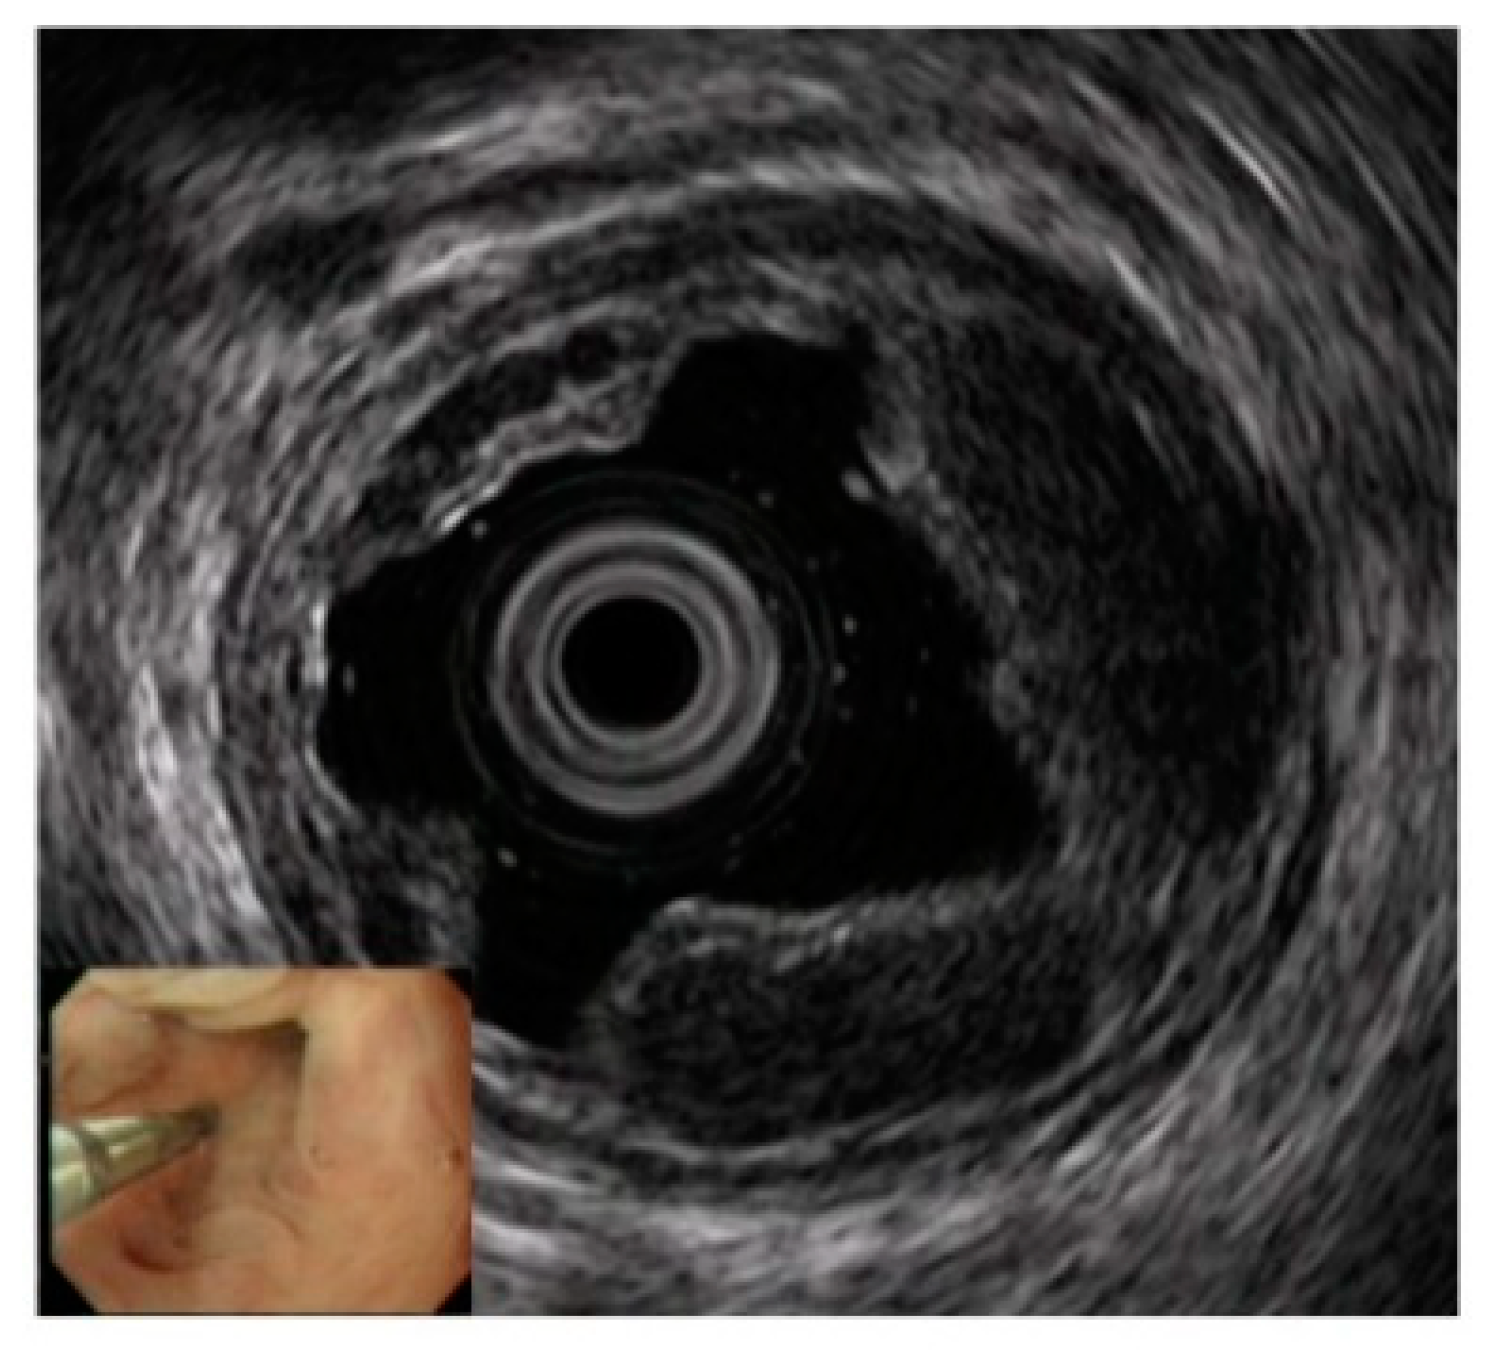

Diagnostics Free FullText The Role of Endoscopic Ultrasound for Endoscopy Detection Esophageal Varices endoscopy is the criterion standard for diagnosing esophageal varices. 1) establishing the stage of cirrhosis, 2) deciding if/when to proceed with upper. upper endoscopy — the most common way to detect varices is with a procedure known as upper endoscopy. This is one of a series of statements discussing. we analysed the endoscopic findings in 1266 patients. Endoscopy Detection Esophageal Varices.

Diagnostics Free FullText The Role of Endoscopic Ultrasound for Endoscopy Detection Esophageal Varices upper endoscopy — the most common way to detect varices is with a procedure known as upper endoscopy. patients with advanced chronic liver disease typically undergo an upper endoscopy to screen for esophagogastric. This is one of a series of statements discussing. endoscopy is the criterion standard for diagnosing esophageal varices. The role of endoscopy in the. Endoscopy Detection Esophageal Varices.

Diagnostics Free FullText The Role of Endoscopic Ultrasound for Endoscopy Detection Esophageal Varices The role of endoscopy in the management of variceal hemorrhage. we analysed the endoscopic findings in 1266 patients with esophageal and gastric varices who underwent upper. patients with advanced chronic liver disease typically undergo an upper endoscopy to screen for esophagogastric. upper endoscopy — the most common way to detect varices is with a procedure known as. Endoscopy Detection Esophageal Varices.

Diagnostics Free FullText The Role of Endoscopic Ultrasound for Endoscopy Detection Esophageal Varices endoscopy is the criterion standard for diagnosing esophageal varices. The role of endoscopy in the management of variceal hemorrhage. patients with advanced chronic liver disease typically undergo an upper endoscopy to screen for esophagogastric. upper endoscopy — the most common way to detect varices is with a procedure known as upper endoscopy. we analysed the endoscopic. Endoscopy Detection Esophageal Varices.